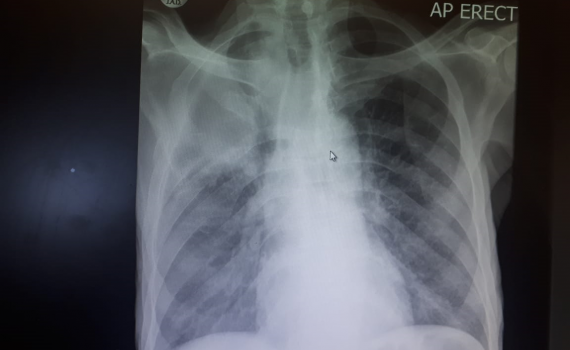

HOSP # MRN63985901 WARD Medical Ward CONSULTANT Dr. Heleen Vreede DOB/AGE 51 year Female Abnormal Result Total calcium of 1.47 mmol/L (2.15 – 2.50) Presenting Complaint The patient has 50

HOSP # WARD Internal Medicine ward CONSULTANT George vd Watt / Heleen Vreede / David Marais DOB/AGE 58 y Male Abnormal Result Upon signing out blood results: Calcium = 50